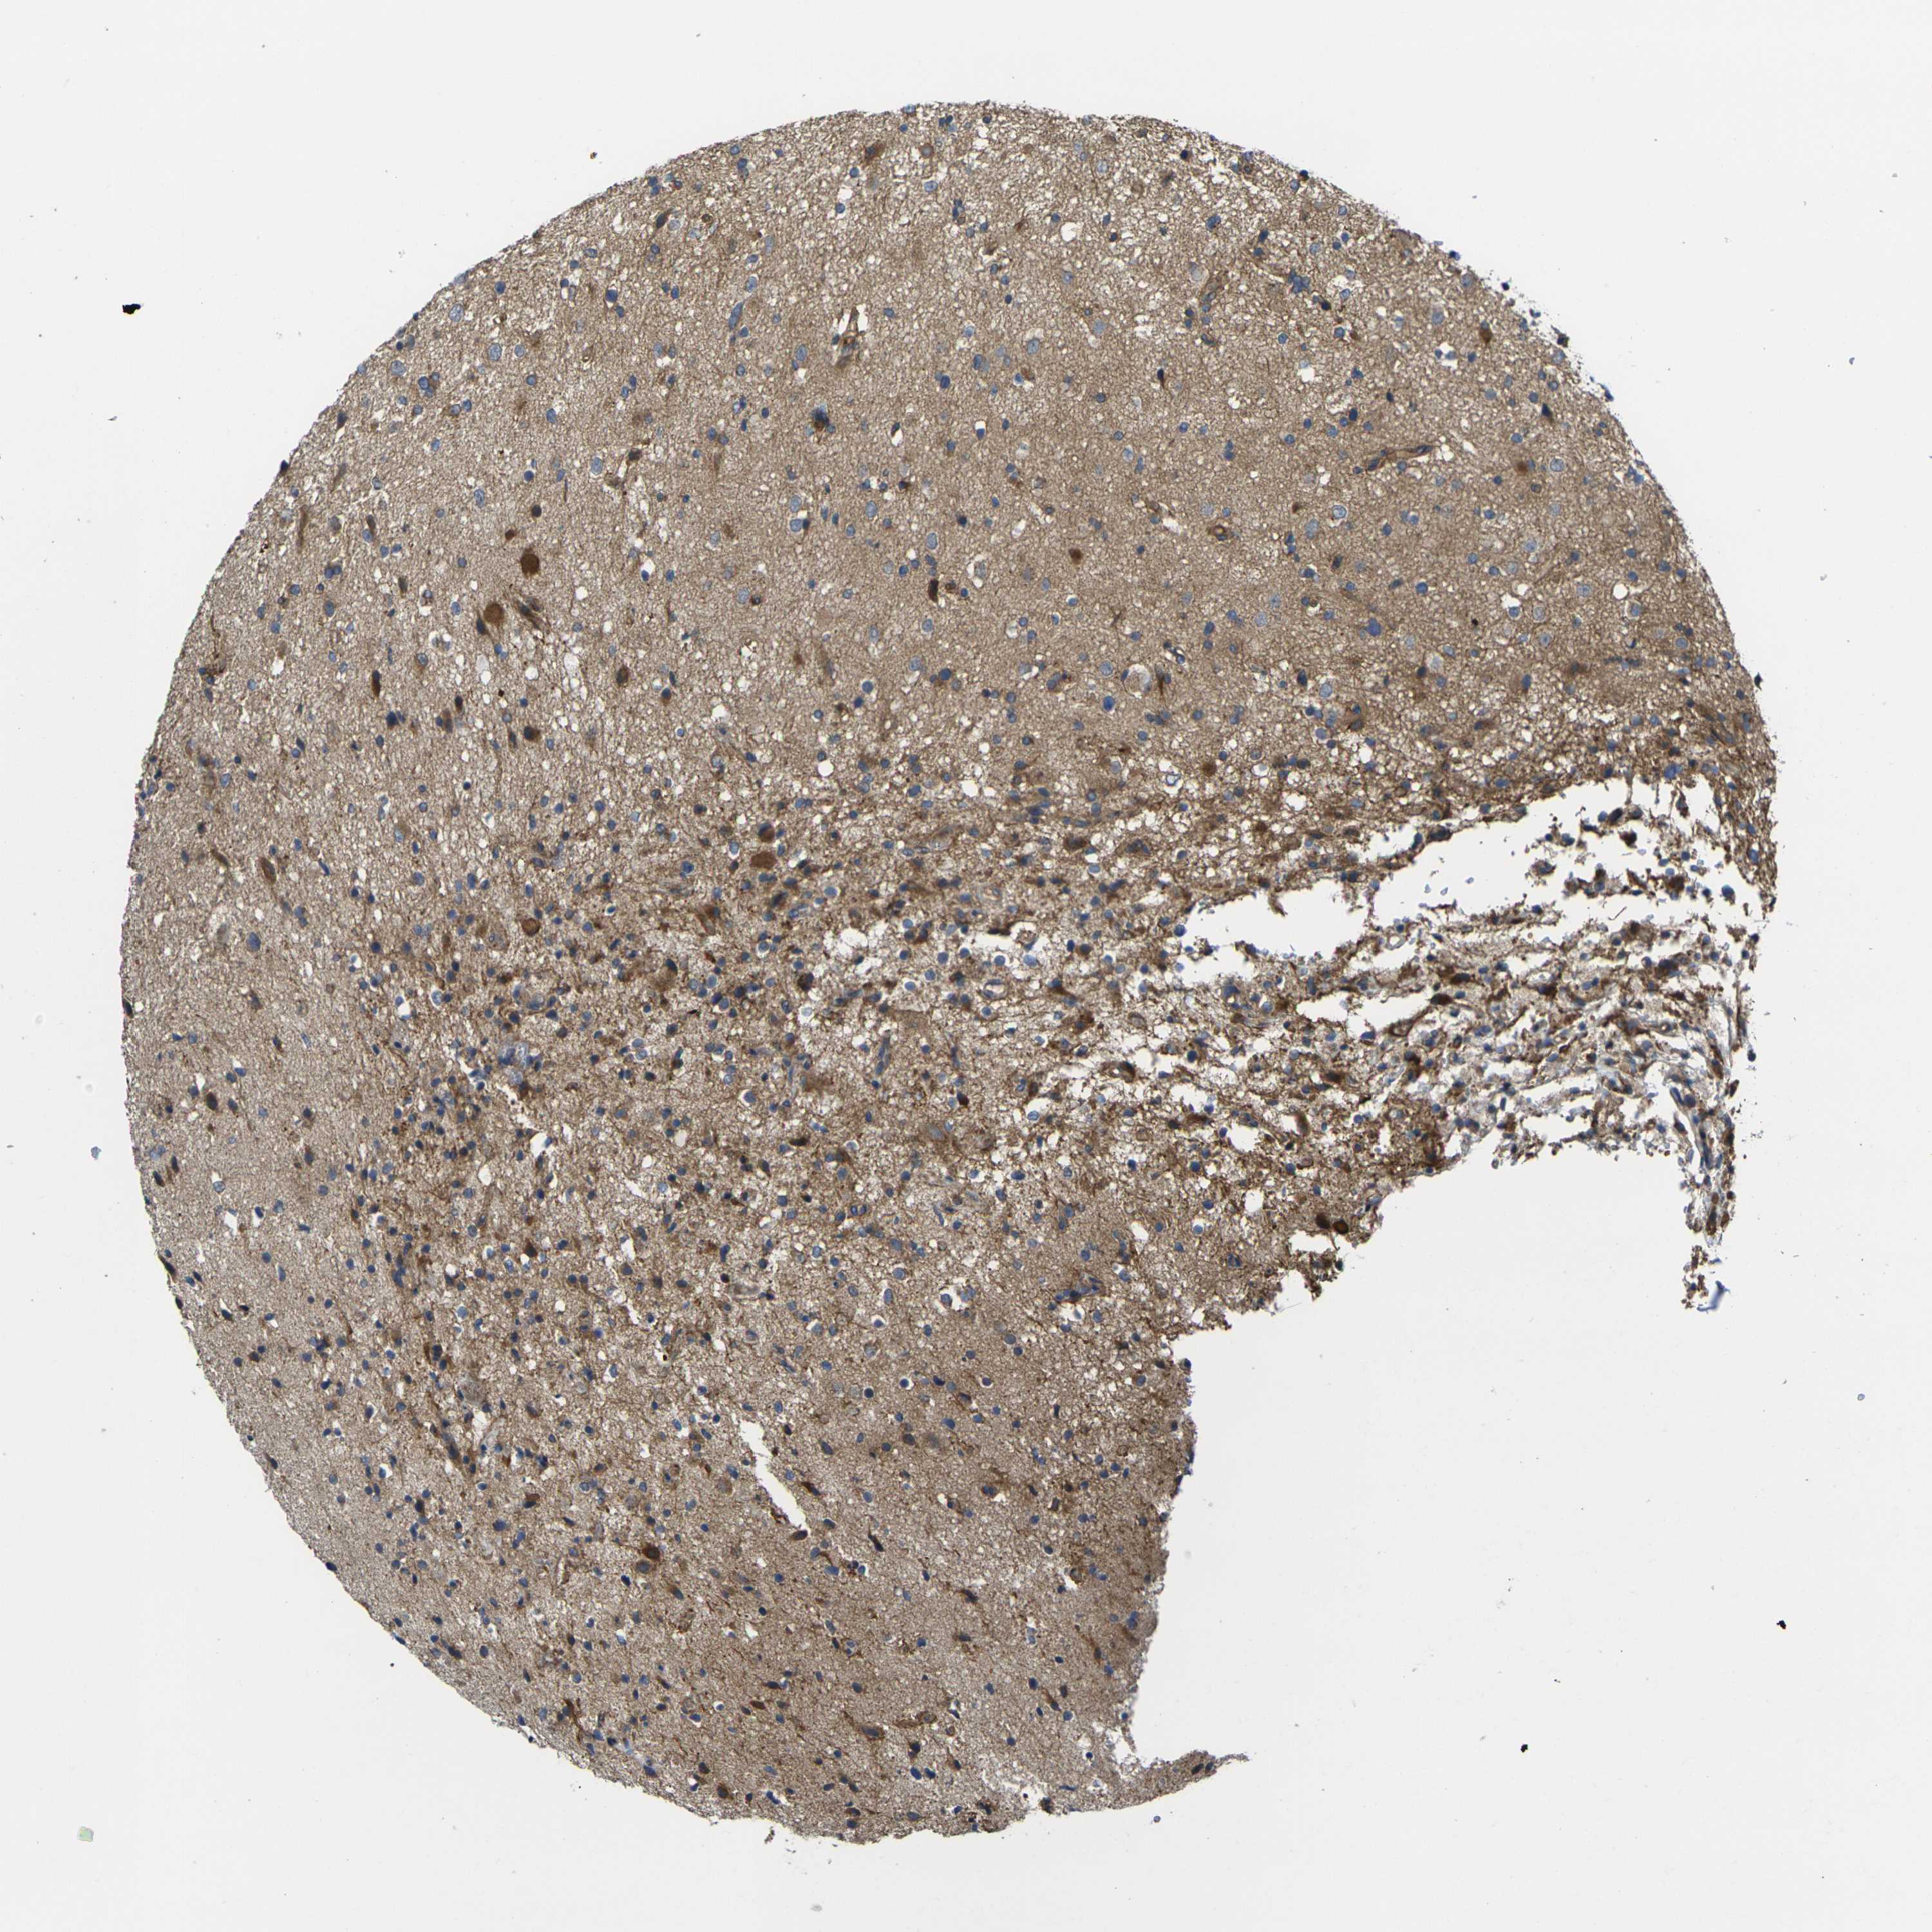

GLIOMA - Protein expressioni

A mouse-over function shows sample information and annotation data. Click on an image to view it in a full screen mode. Samples can be filtered based on level of antibody staining by selecting one or several of the following categories: high, medium, low and not detected. The assay and annotation is described here.

Note that samples used for immunohistochemistry by the Human Protein Atlas do not correspond to samples in the TCGA dataset.

Antibody stainingi

Antibody staining in the annotated cell types in the current human tissue is reported as not detected, low, medium, or high, based on conventional immunohistochemistry profiling in selected tissues. This score is based on the combination of the staining intensity and fraction of stained cells.

Each image is clickable and will lead to virtual microscopy that enables deeper exploration of all samples and also displays staining intensity scores, fraction scores and subcellular localization as well as patient and tissue information for each sample.

Antibody CAB013008

Staining

High

Medium

Low

Not detected

Intensity

Strong

Moderate

Weak

Negative

Quantity

>75%

75%-25%

<25%

None

Location

Nuclear

Cytoplasmic/membranous

Cytoplasmic/membranous,nuclear

Glioma, malignant, High grade

Glioma, malignant, Low grade